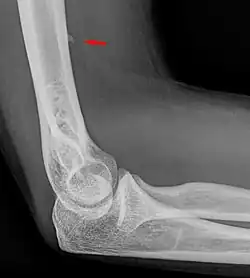

Kleiner Processus supracondylaris im seitlichen Röntgenbild des Ellenbogens.

Der Processus supracondylaris ist eine seltene atavistische Bildung an der vorderen ulnaren Seite des distalen Endes des Oberarmknochens (Humerus), etwa 6 bis 7 cm proximal des Gelenkspaltes. Synonyme sind Processus supracondylicus, Tuberculum supratrochleare, Humerussporn und englisch Humeral supracondylar spur. Es handelt sich um einen knöchernen Fortsatz, der bei 0,7 % – 2 % aller Menschen vorkommt.[1] Die Erstbeschreibung geht auf den Anatomen F. Tiedemann im Jahre 1822 zurück.[2] (zitiert nach[3])